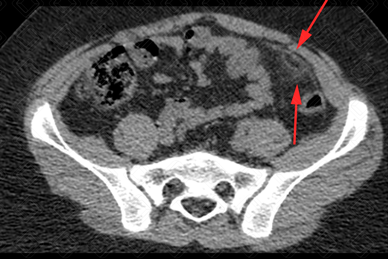

Texto alternativo para a imagem Figuras 1 e 2. Créditos: Dra. Elazir Mota - Rio de Janeiro/RJ

Descrição das figuras 1 e 2: Tomografia computadorizada do abdome superior e pelve. Observa-se uma imagem ovalada, hipodensa, com conteúdo interno gorduroso, na borda anti- mesentérica do cólon, sendo mais comum à esquerda (setas vermelhas). Em geral, associam-se à densificação dos planos adiposos no mesentério.

• Tomografia computadorizada do abdome : Imagem ovalada, paracólica, medindo cerca de 1 a 5 cm, com densidade de gordura e centro radioluscente. Densificação dos planos adiposos perilesional também habitualmente é observada (figura acima).